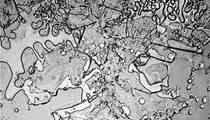

هل تعلم أن لكل دمعة تركيبة وحكاية ؟

" ، شابّة أرادت معرفة ما إذا كانت دموع الحزن مختلفة عن دموع الفرح التي تسقط من عيونها، فلجأت الى جهاز المجهر أو ما يعرف بالـ"ميكروسكوب" لإكتشاف الجواب.

وأجرت روز بحثاً على 100 نوع من الدموع، ووجدت أن الدمعة التي يفرزها الجسم لترطيب العين في الحالات الطبيعية مختلفة تماماً عن تلك التي تسقط أثناء تقطيعنا للبصل. كما أن دموع الفرح التي تَنتُج عن فرط الضحك هي مختلفة تماماً عن دموع الحزن.

هكذا فكل دمعة تسقط من أعيننا تحمل في ثناياها صورة مصغرة عن خبرات الإنسان في حياته من فرح أو حزن أو معاناة.

وقد أطلقت روز على دراستها تسمية " The Topography of Tears "، أو "علم ملامح الدموع".

في المقابل، تحتوي هذه الأنواع المختلفة من الدموع على جزيئات متميزة. فالدموع العاطفيّة تتضمن "البروتين" الناتج عن هرمونات معينة، يفرزها الجسم حين يكون الانسان في حالة عصبيّة. أما الدموع الاخرى التي تم فحصها تحت المهجر، تُظهر تركيبة مختلفة من الجزئيات.